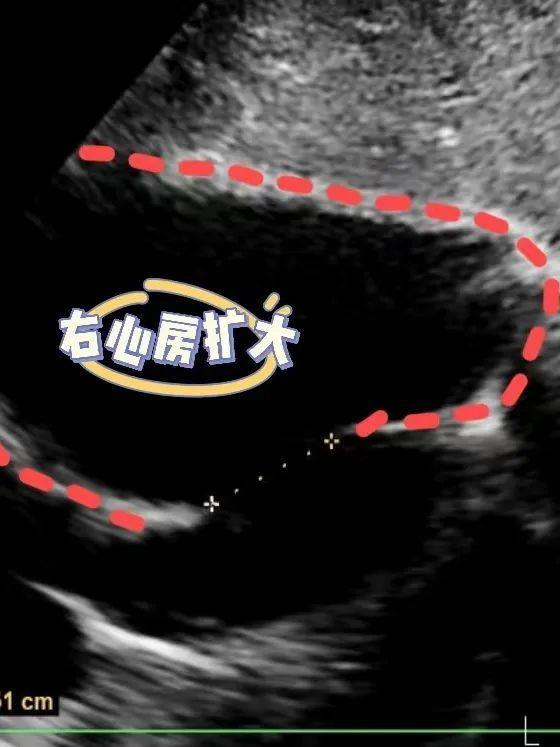

例如,心脏彩超主要检查房子(心房/室)是否增大,墙壁(房/室壁)是否增厚,墙壁是否出现孔洞(房/室缺),门窗(房室瓣、半月瓣)是否关闭良好,以及房子的稳固情况(心功能)等。

心脏彩超下的右心房扩大